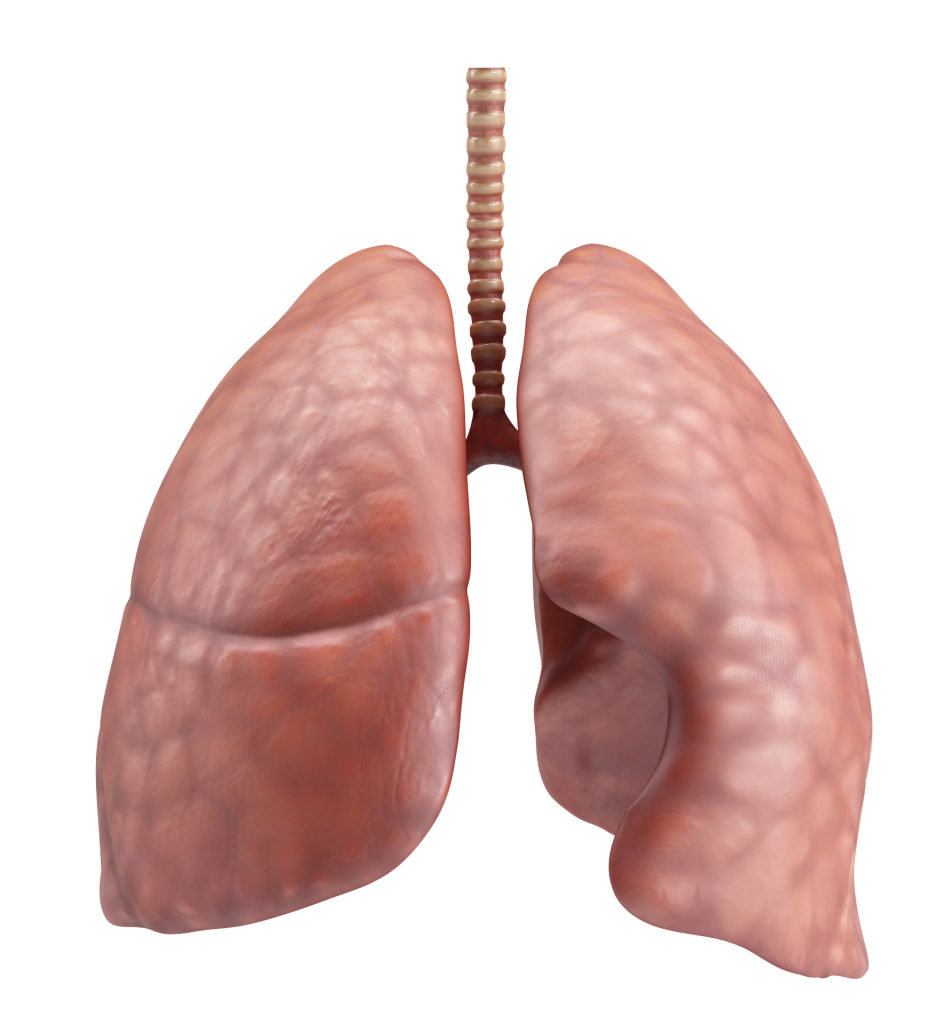

AKCİĞER

Nefes alıp-verme yoluyla temiz havanın vücut içine alınmasını ve kirli havanın vücut dışına atılmasını sağlayan organlardır. Akciğerler, göğüs kafesi içinde yer alan pembe renkli, süngerimsi görünüşte organlardır. Akciğerler, sağ ve sol olmak üzere iki bölümden oluşur. Sol taraftaki akciğer, hemen altında kalp bulunduğu için daha küçüktür.